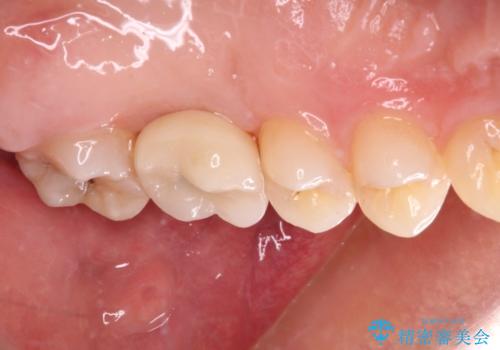

奥歯の虫歯は抜歯が必要であったので、矯正治療前に抜歯をし、矯正治療と並行してインプラントによる補綴治療を行うこととしました。

当院の特徴は、矯正治療とインプラント補綴治療の担当医が同じ歯科医師であるため、両方の治療を並行して行うことができます。